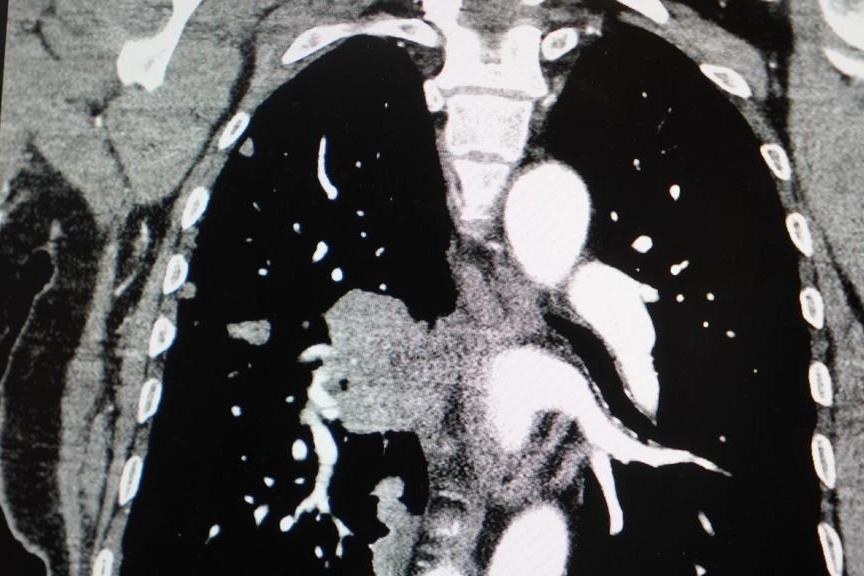

"KADINLARDA AKCİĞER KANSERİ VAKALARI BELİRGİN ŞEKİLDE ARTIYOR"

Akciğer kanseri vakalarındaki artışa da dikkat çeken Özkaya, "Son yıllarda hem sigara içen hem de hiç sigara kullanmamış bireylerde akciğer kanseri vakalarında dikkat çekici bir artış görüyoruz. Özellikle kadınlarda adenokarsinom tipi akciğer kanseri belirgin şekilde artış göstermektedir., Yapılan son araştırmalara göre akciğer kanseri teşhislerinin yaklaşık yüzde 20'si hiç sigara içmemiş bireylerde konuluyor. Bunun en önemli nedeni pasif içiciliktir. Yani siz sigara içmeseniz bile, yakın çevrenizde sigara içiliyorsa akciğer kanseri riskiyle karşı karşıya kalabilirsiniz" ifadelerini kullandı.